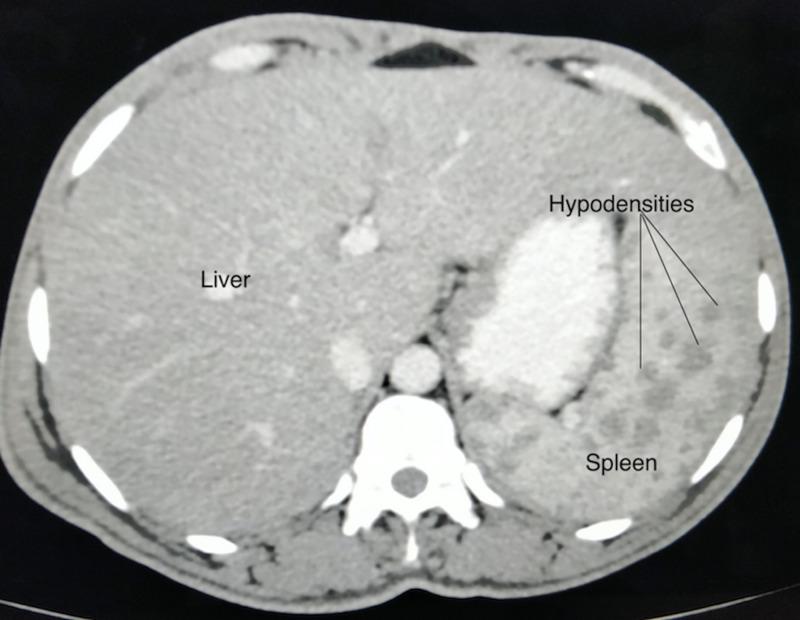

Tuberculosis is an established cause of pyrexia of unknown origin and can implicate practically any human organ system. Splenic involvement is common in disseminated or miliary tuberculosis following hematogenous spread, but isolated splenic involvement is a very rare phenomenon. We report the case of a 30-year-old immunocompetent female who presented with high-grade fever and dull aching pain in the left hypochondrium for three months. Laboratory data provided no diagnostic information. Abdominal ultrasonography revealed an enlarged spleen with multiple small hypoechoic lesions that were corroborated on computed tomography. No pulmonary involvement or primary focus of infection was discernible elsewhere. Splenic fine needle aspiration cytology helped clinch a histopathological diagnosis of isolated splenic tuberculosis. Administration of anti-tubercular therapy resulted in resolution of the disease and an excellent outcome in our patient.

结核病是不明原因发热的既定病因,几乎可累及人体任何器官系统。脾受累在血行播散性或粟粒性结核病中很常见,但孤立性脾受累是一种非常罕见的现象。我们报告一例30岁免疫功能正常的女性病例,她出现高热和左季肋部钝痛3个月。实验室检查未提供诊断信息。腹部超声显示脾脏肿大,有多个小的低回声病变,计算机断层扫描证实了这一点。其他部位未发现肺部受累或感染原发灶。脾脏细针穿刺细胞学检查有助于确诊孤立性脾结核的组织病理学诊断。给予抗结核治疗使疾病得到缓解,我们的患者预后良好。